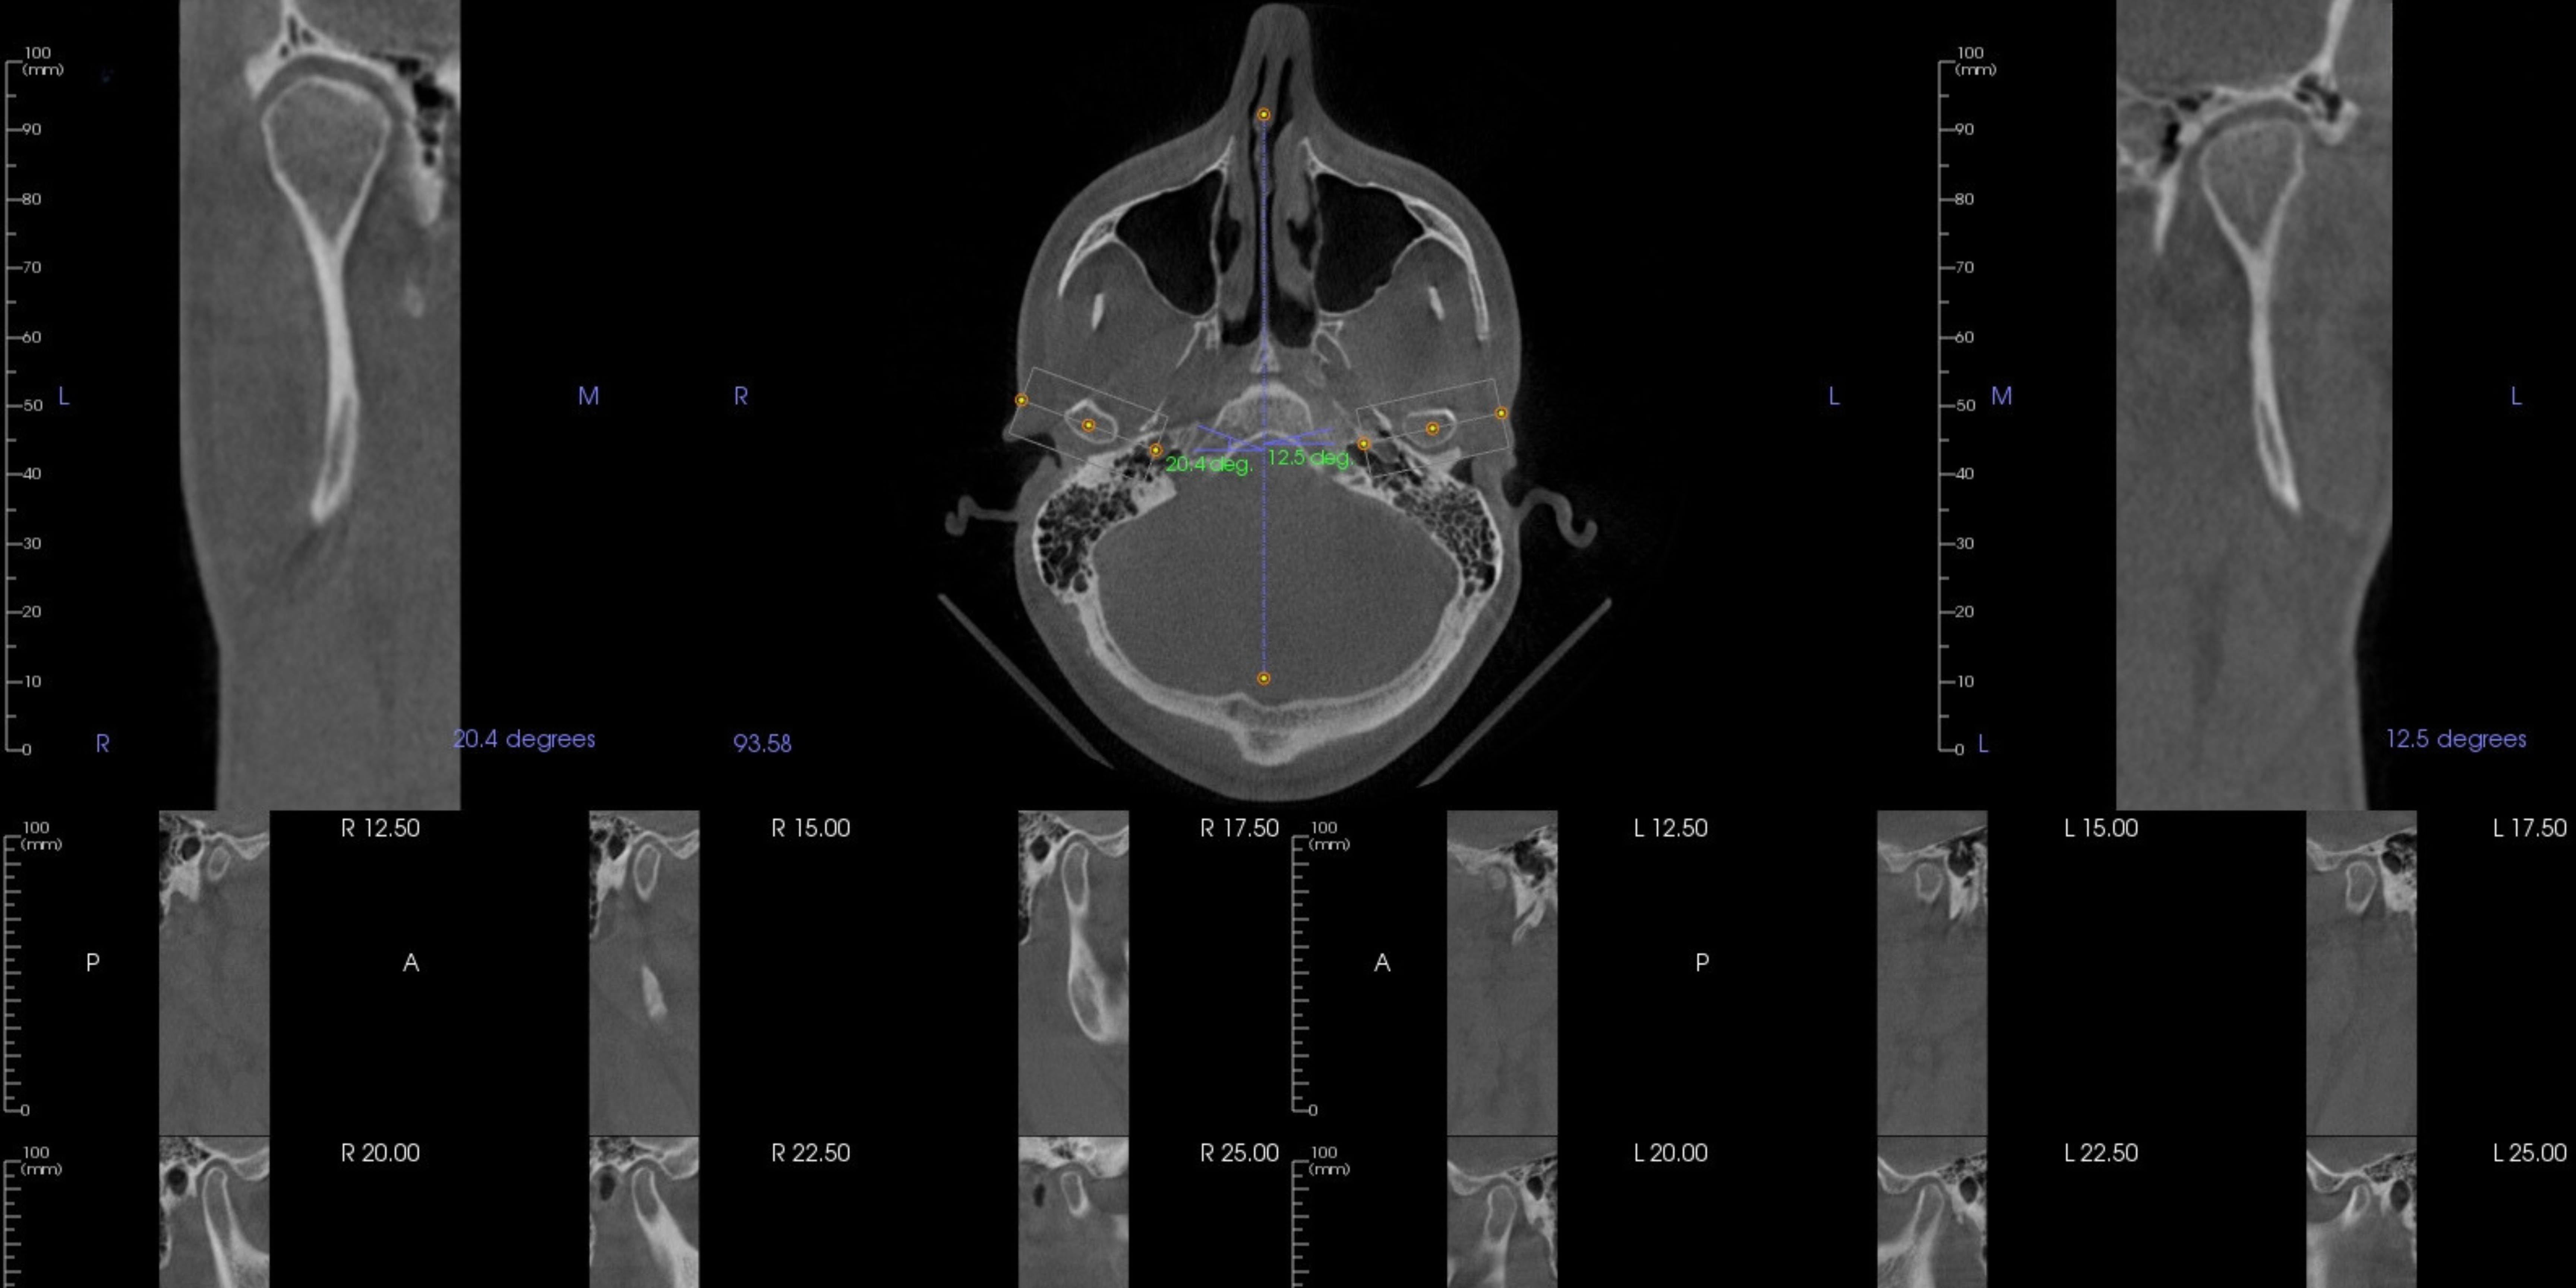

Jaw, Head, Neck Pain (TMJ) Pain and Occlusion

TMJD (Temporomandibular Joint Disorder) pain refers to discomfort or pain in the jaw joint and the surrounding muscles. Occlusion relates to the alignment and contact between the upper and lower teeth when the jaws are closed, and issues with occlusion can contribute to TMJ pain and discomfort in the head and neck. When the occlusion is in balance with the nerve and muscle activity, we can alleviate pain, muscle tension, clenching, bruxism, headaches, migraines while enhancing a person’s ability to chew and digest food efficiently.

At Reclaim Integrative Dentistry, we incorporate the philosophies of neuromuscular dentistry, which searches for and treats the appropriate and ideal alignment of muscles, bones and teeth.